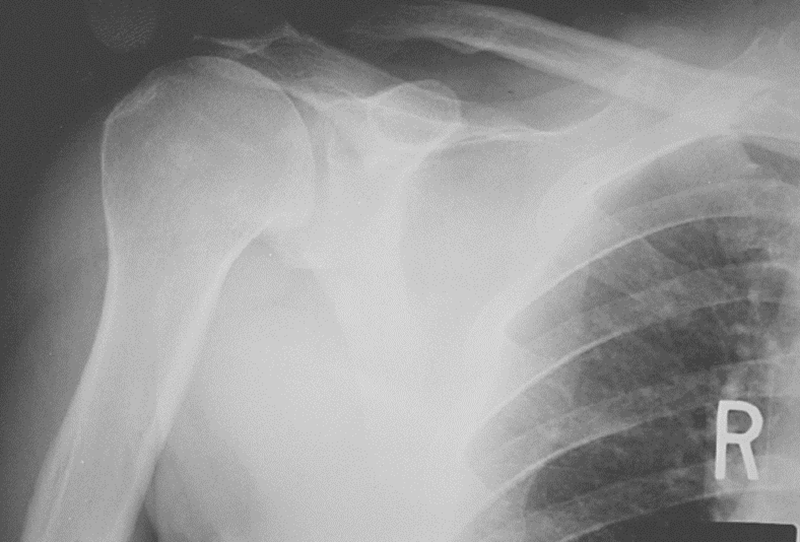

1、X线检查

X线检查用来评估肩峰形态,肱骨头和肩盂的关系,以及除外其他疾病。

图16 巨大肩袖损伤,肩峰下间隙<9mm